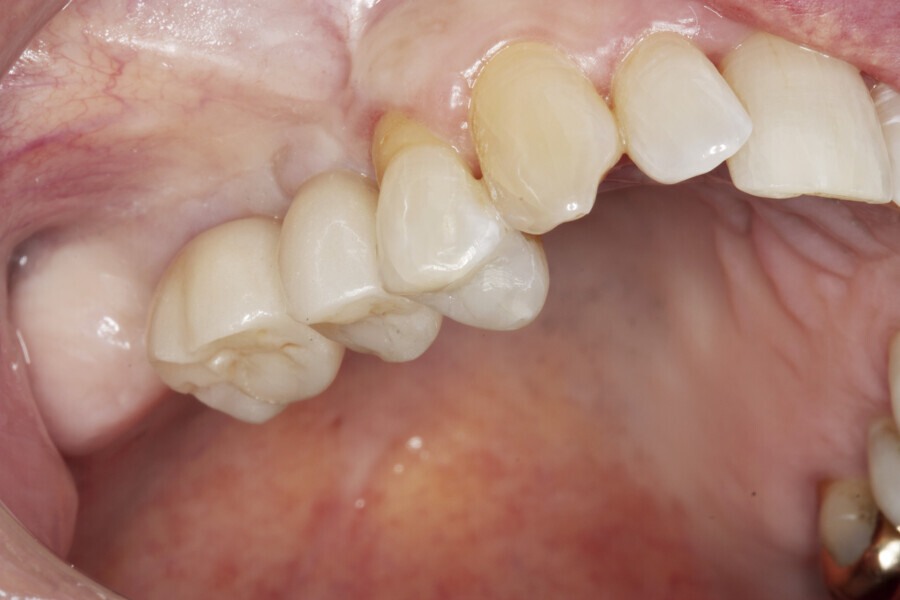

A 64-year-old female patient presented to our practice with a heavily restored dentition. Her failing maxillary right first molar and second premolar had been extracted by her general dental practitioner (Fig. 1), leaving an unbounded edentulous area. Radiographic assessment indicated that there was ample bone depth in the posterior maxilla to allow for satisfactory implant placement (Fig. 2). An implant solution was provided using two individual screw-retained crowns supported by two OmniTaper EV implants (Dentsply Sirona) and using a digital workflow with Primescan and Atlantis (Dentsply Sirona).

A digital impression using an intra-oral scanner (Primescan) was then captured using the Atlantis IO FLO for a digital restorative workflow (Fig. 13). An Atlantis CustomBase solution, consisting of an Atlantis crown, an Atlantis abutment and an Atlantis abutment screw, was fabricated for each implant and tried in, and no adjustments were needed (Figs. 14 & 15). After seating, a radiographic evaluation was performed to verify the final restorations (Fig. 16). The final restorations showed excellent soft-tissue adaptation and an aesthetic outcome (Figs. 17 & 18). The patient was extremely satisfied with the outcome of the treatment and the fixed restorations.

Fig. 17: Screw access holes sealed and amalgam in tooth #14 replaced with composite.

Fig. 18: Final restorations in situ.